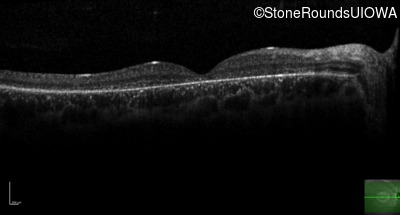

AR Stargardt Disease (IIA)

AR Stargardt Disease (IIA)

| AR Stargardt Disease | ABCA4 | Leu541Pro CTA>CCA, Ala1038Val GCC>GTC | Gln1003Stop CAG>TAG | AR |